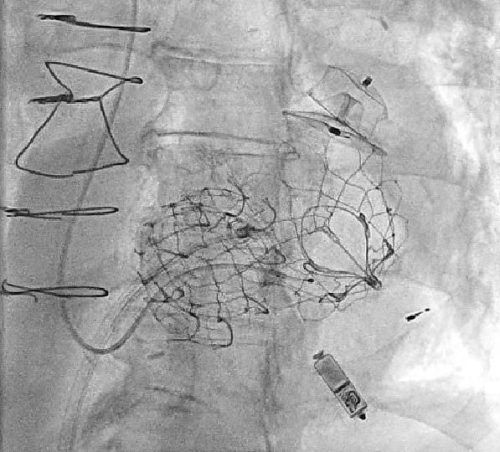

In seiner Brust schlägt ein Kämpferherz: Georg Schneid (rechts) lässt sich von Professor Markus Krane (Mitte) und Dr. Hendrik Ruge (links) die Hightech-Implantate erklären.

Hightech zum Überleb